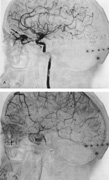

In some persons, the cavernous sinuses have existing or potential connections to the deep venous system of the brain. Indeed, this may be the preferential route of venous drainage from all or part of the cavernous basal sinus complex. Therefore, the clinical appearance of orbital venous hypertension associated with a cavernous dAVM may be relatively minimal, but arterialized flow is transmitted instead chiefly via venous dural channels draining the medial aspects of the temporal lobes and the basal vein of Rosenthal. The latter drains an extensive deep parenchymal territory, including part of the posterior fossa. This effluent pattern explains how some cavernous dAVMs or CCFs present with relatively minor outward physical signs but with serious complications from cortical venous hypertension (Fig. 18), elevated intracranial pressure (a form of secondary pseudotumor cerebri syndrome; see Chapter 5, Part II), temporal lobe seizures, brain parenchymal hemorrhage caused by venous infarction or venous rupture (Fig. 19), or edema of the posterior fossa structures.119

Fig. 18. A 25-year-old man developed severe right-sided proptosis and a loud bruit at the time of a vehicular accident. Lateral projection of the right internal carotid artery in the early arterial phase (A) and late arterial phase (B) in anteroposterior projection demonstrate immediate opacification of the superior and inferior ophthalmic veins (straight arrows), the inferior petrosal sinuses (curved arrows) and of the deep parenchymal veins of the right hemisphere (open curved arrows). The fistula was related to a large carotid laceration involving the cavernous and supraclinoid segments of the right internal carotid artery. The artery could not be preserved at the time of treatment. C: Latex balloons (open-ended arrowheads) were placed in the fistula and within the carotid artery at the time of treatment. (Courtesy of Frank Huang-Hellinger)

Fig. 19. A 30-year-old woman presented with headaches. Lateral views of left (A) and right (B) internal carotid arteriograms demonstrate developmental venous malformation of the cribriform plate supplied by both ophthalmic arteries. Note subarachnoid veins of the anterior cranial fossa (curved arrows). In addition, the right ophthalmic artery (B) has a cavernous origin (arrow), a vestige of the dorsal ophthalmic artery that usually atrophies in fetal development.